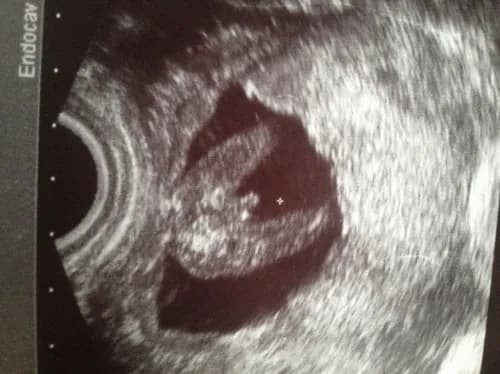

Tag kiedy można poznać płeć dziecka na usg